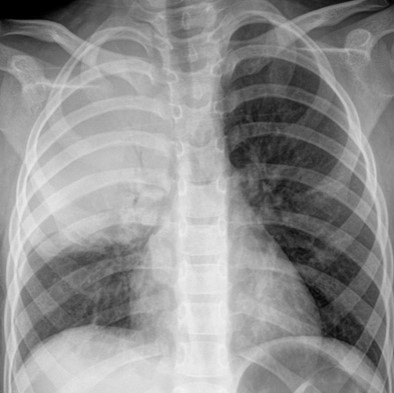

Neumonía bacteriana en lóbulo superior derecho.

La neumonía bacteriana se presenta habitualmente como un patrón alveolar de márgenes mal definidos, con tendencia a confluir, y de distribución segmentaria o lobar. A veces presenta el signo del broncograma aéreo, por el contraste entre la vía aérea y el espacio aéreo ocupado. Puede asociar derrame pleural6-8.